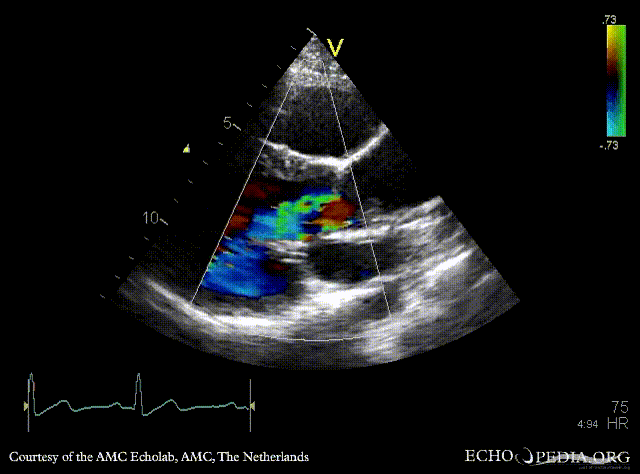

PSAX: bicuspid aortic valve PSAX with Color Doppler: severe aortic regurgitation